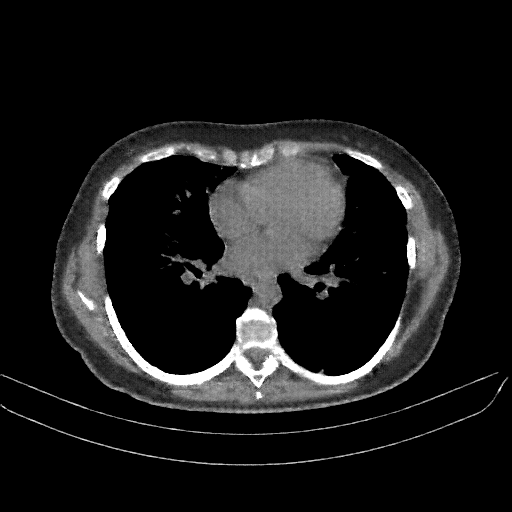

Reconstructed NATIVE CT scan (cycle consistency)

No window - Raw intensity values

Lung window (WL -600, WW 1500 β†’ Low βˆ’1350, High +150)

Mediastinum window (WL 40, WW 400 β†’ Low βˆ’160, High +240)